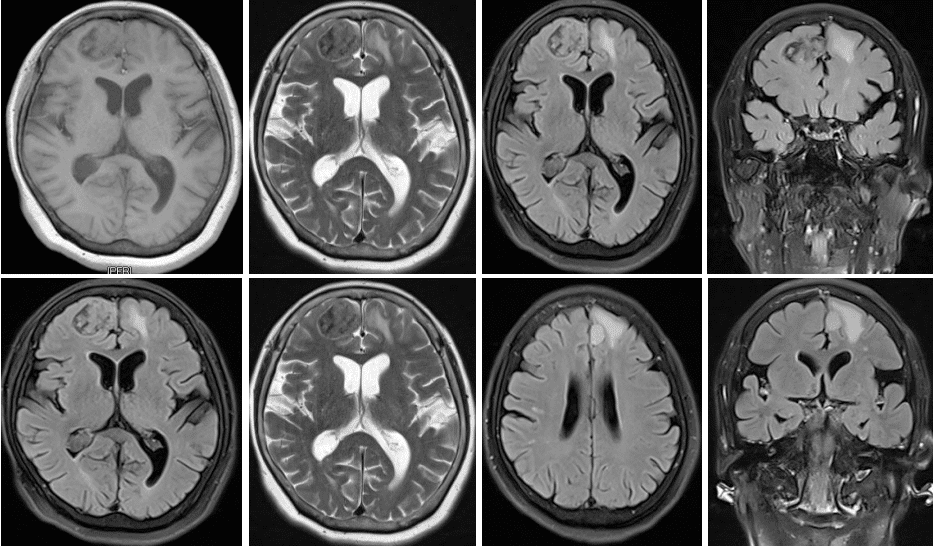

头MRI(2023-11-22)右侧额叶可见团片状等低混杂信号影,边界较清,大小约为3.0x2.2cm。左侧额部镰旁可见椭圆形稍长T1稍长T2信号结节影,FLAIR呈高信号,边界较清,大小约为1.3x1.0cm,周围可见斑片状水肿信号影。